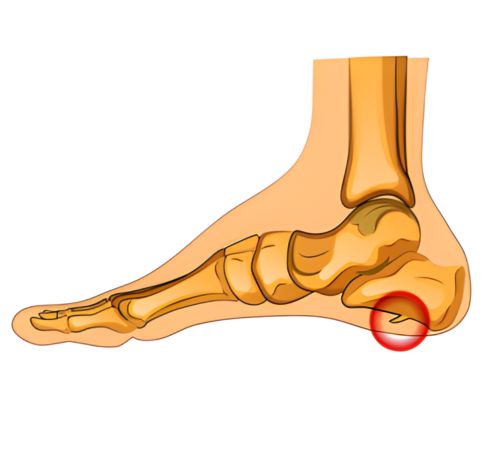

O esporão de calcâneo é uma condição que gera muitas dúvidas e, frequentemente, muita dor. Trata-se de um crescimento ósseo anormal, semelhante a uma pequena ponta ou espora, que se forma no osso do calcanhar (o calcâneo), geralmente na parte de baixo, onde a fáscia plantar se prende. Embora o nome assuste, é importante saber que nem sempre a presença do esporão causa dor; muitas pessoas o têm e não sentem absolutamente nada.

O surgimento do esporão está diretamente ligado à tensão crônica e repetitiva sobre a fáscia plantar e os músculos do pé. Com o tempo, essa sobrecarga causa microlesões e inflamação na região onde esses tecidos se inserem no osso do calcanhar. Como resposta do organismo para tentar reparar e reforçar essa área, ocorre uma deposição gradual de cálcio, formando o esporão ósseo ao longo de meses ou anos.

O diagnóstico é feito pelo ortopedista, que irá avaliar seus sintomas, histórico e examinar seu pé para identificar os pontos de dor. O exame de raio-X é essencial para confirmar a presença do esporão ósseo, visualizando a pequena protuberância no calcanhar. No entanto, é importante lembrar que a dor muitas vezes é causada pela inflamação dos tecidos ao redor (fascite), e não pela ponta óssea em si.